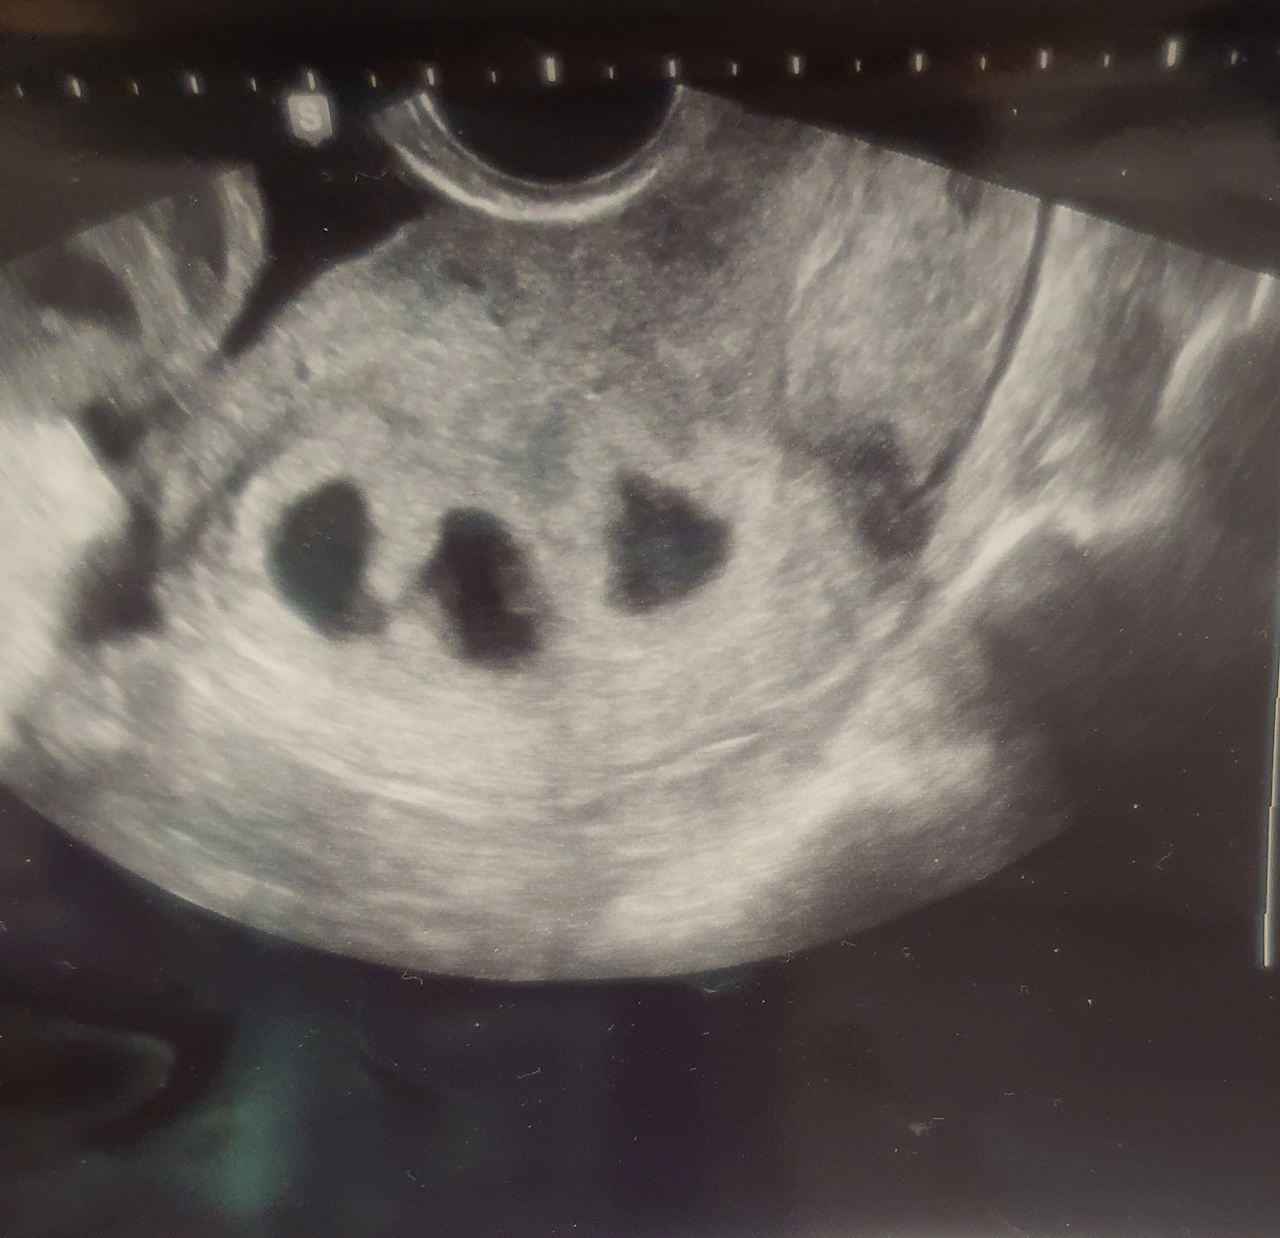

5주 0일.

초음파를 보던 의사의 손이 바빠진다. 이리저리 돌려 보더니 어디론가 급하게 전화를 건다.

“나진님 2개 이식한 것 맞지?”

아기집이 3개 생겼단다.

“하나가 분열해서 쌍둥이가 되었어요. 그래서 최종적으로 세쌍둥이가 되었어요.”

수정란 하나가 초기 분열하여 아기집을 따로 쓰는 일란성쌍둥이가 되었다고 했다. 일란성쌍둥이 둘에 이란성쌍둥이 하나, 이렇게 세쌍둥이를 임신하게 되었다. 세쌍둥이부터는 고위험이라 선유(선택적 유산)를 해야 한다고 했다. 보통 8주 안에 알아서 정리되는 경우(도태 또는 소실)도 많으니 그렇게 되면 다행이고 아니면 엄마가 결정해야 한단다. 남편과 잘 상의하고 다음 주에 오라고 했다.

알콩이 달콩이 콩콩이의 집

저는 일란성쌍둥이가 빨리 분열을 하고, 셋이 거의 동시에 착상을 한 것 같습니다. 그래서 5주 0일에 바로 아기집 3개가 보였습니다. 시간차를 두고 착상을 하는 경우에는 처음에는 세쌍둥이인 걸 모를 수도 있습니다. 실제로 5주에는 아기 한 명, 6주에 갔더니 두 명, 7주에 세 명의 아기를 확인하게 된 케이스도 많습니다. 은 처음엔 쌍둥이만 보였다가 다음 주에 갔을 때 뿅 하고 나머지 한 명이 더 보이는 경우도 있습니다. 보통 5주~8주 사이에 알게 됩니다.